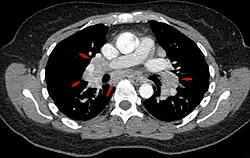

Hilar adenopathy especially on the person's left (AP CXR)

Hilar adenopathy especially on the person's left (lateral CXR)

Hilar adenopathy especially on the person's left (coronal CT)

Hilar adenopathy especially on the person's left (transverse CT)